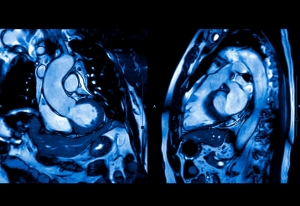

ΣΥΝΔΡΟΜΟ ΜΑΚΡΟΥ QT

Το Σύνδρομο Μακρού QT αποτελεί κύρια αιτία αιφνίδιου θανάτου σε νεαρά άτομα, με συχνότητα εμφάνισης που υπερβαίνει το 1 στα 2000. Η κλινική σημασία της έγκαιρης διάγνωσης